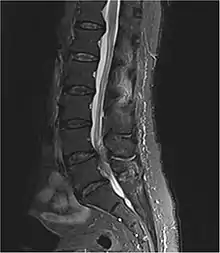

常見主要成因為下背椎間盤突出。其他成因包含椎管狹窄、癌症、創傷、硬腦膜上膿瘍、及硬腦膜上血腫[1][2]。其診斷方式主要根據症狀,確診方式為醫學影像,如核磁共振(MRI)、或電腦斷層掃描[1][3]。

臨床病史和理學檢查可提供初步診斷的依據,確診則必須透過核磁共振(MRI)或電腦斷層掃描等醫學影像進行[4]。在進行MRI之前,可以透過膀胱超音波來檢視患者是否有尿滯留。另外在插入尿管時若患者沒有感覺,也可能可以加強馬尾症候群的診斷。